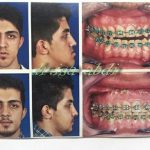

– متخصص جراحی فک , پلاستیک صورت و بینی

جراحی فک , پلاستیک , صورت وبینی

جراحی ترمیمی و زیبایی فک و صورت و جمجمه و گردن